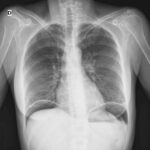

En cuanto a la evaluación anatómica, la resonancia magnética es particularmente útil, ya que permite visualizar las estructuras blandas y detectar la presencia de una banda fibrosa o costilla cervical que esté comprimiendo el plexo braquial. Las radiografías simples o la tomografía computarizada (TAC) pueden mostrar la existencia de una costilla cervical o de una apófisis transversa anormalmente larga en la séptima vértebra cervical. Sin embargo, es importante destacar que la ausencia de hallazgos en estas imágenes no excluye la presencia de una banda fibrosa, que puede ser de difícil detección mediante estas técnicas.